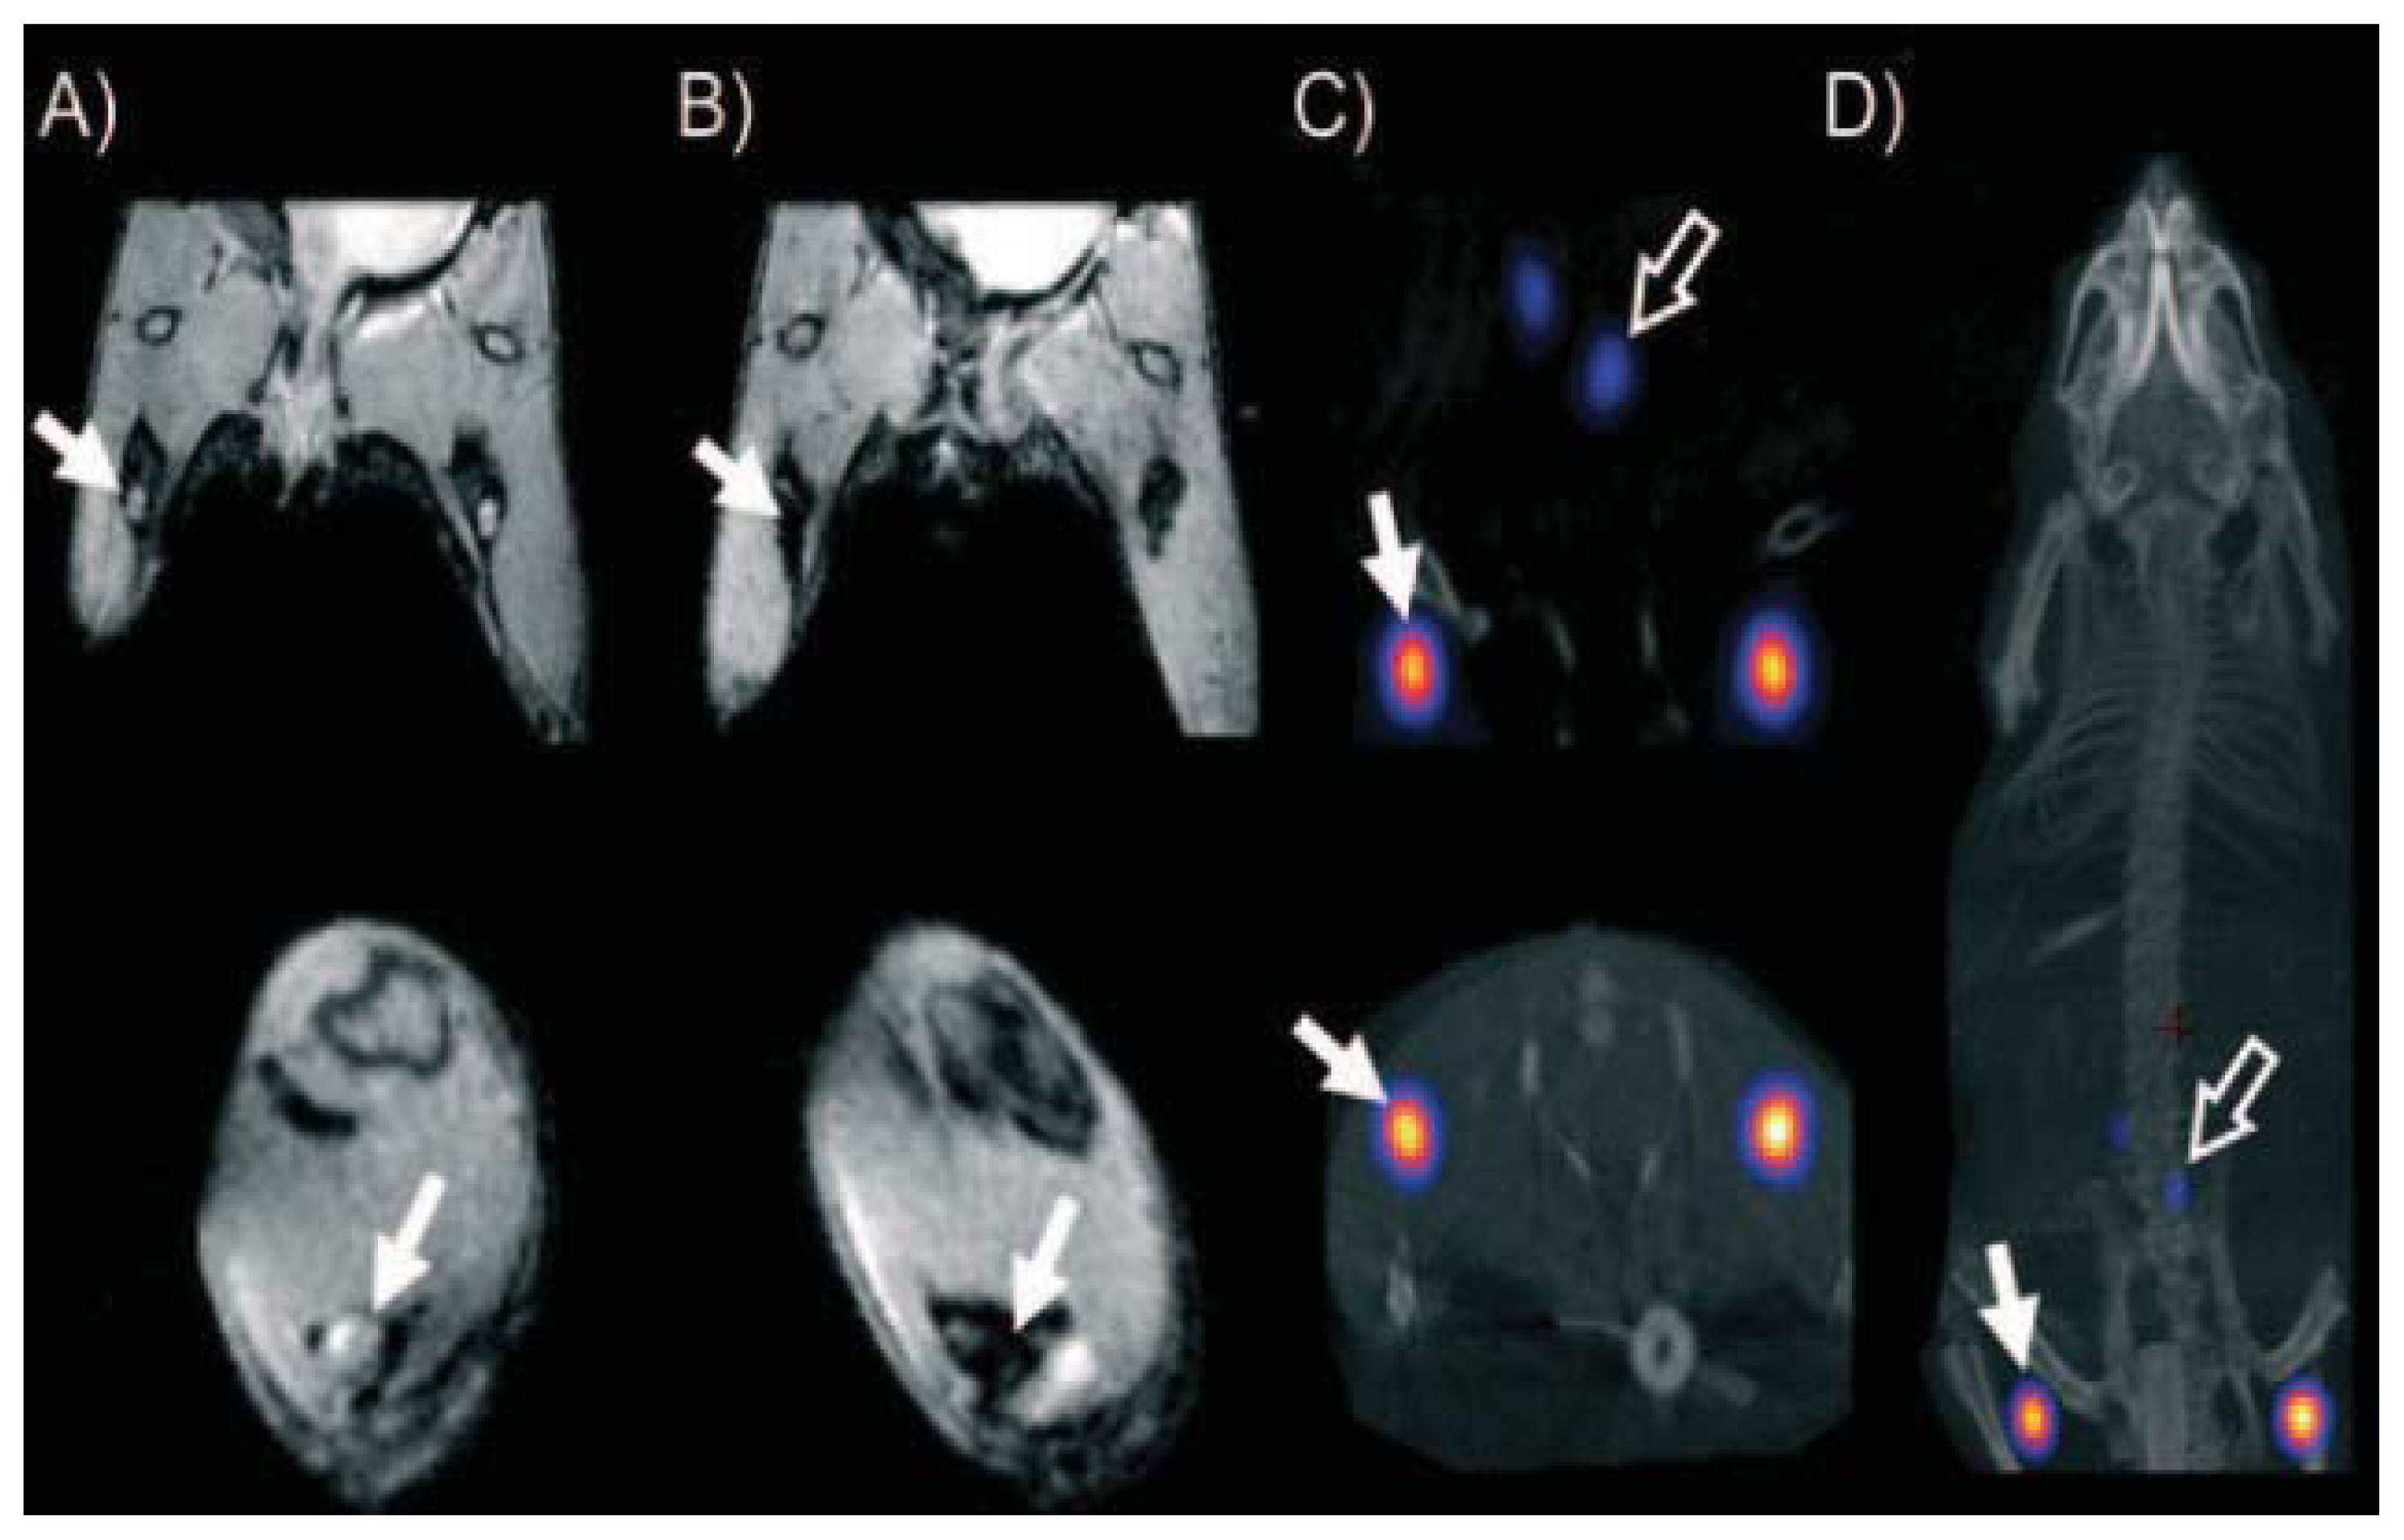

- Lee, H.Y.; Li, Z.; Chen, K.; Hsu, A.R.; Xu, C.; Xie, J.; Sun, S.; Chen, X. Pet/mri dual-modality tumor imaging using arginine-glycine-aspartic (rgd)-conjugated radiolabeled iron oxide nanoparticles. J. Nuclear Med 2008, 49, 1371–1379. [Google Scholar]

- Torres Martin de Rosales, R.; Tavare, R.; Paul, R.L.; Jauregui-Osoro, M.; Protti, A.; Glaria, A.; Varma, G.; Szanda, I.; Blower, P.J. Synthesis of 64cu(ii)-bis(dithiocarbamatebisphosphonate) and its conjugation with superparamagnetic iron oxide nanoparticles: In vivo evaluation as dual-modality pet-mri agent. Angew. Chem. Int. Ed. Engl 2011, 50, 5509–5513. [Google Scholar]